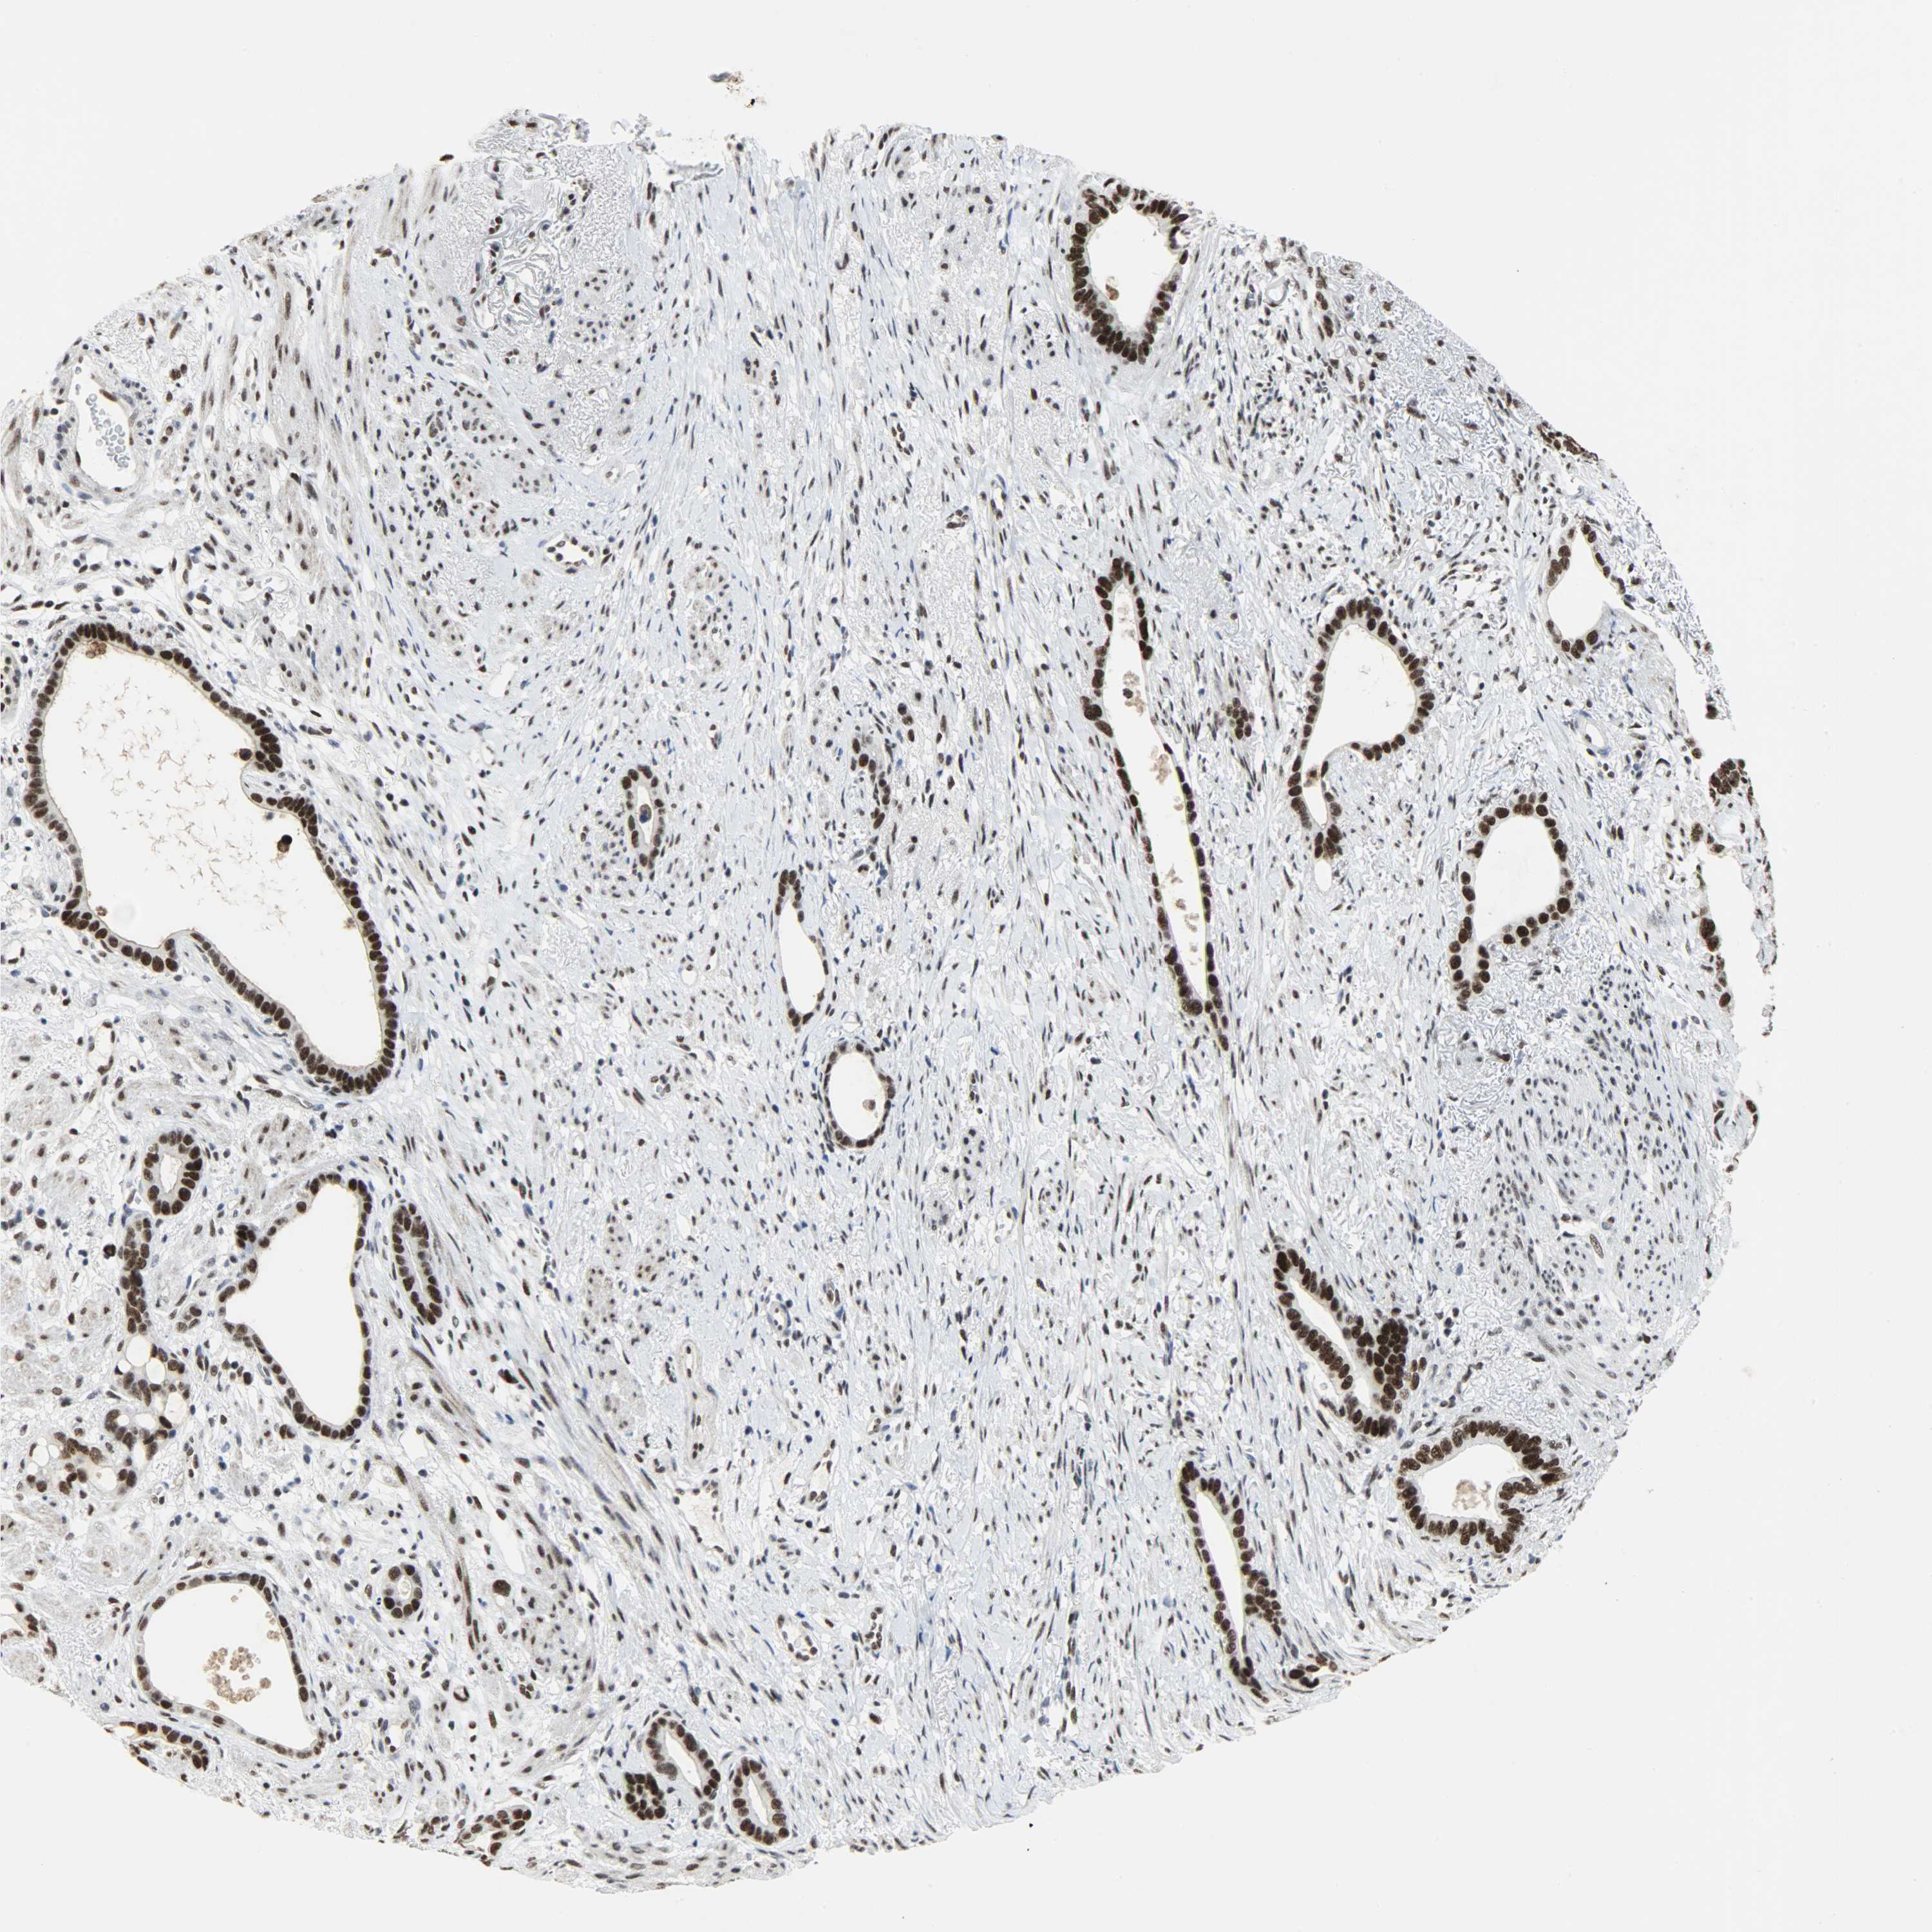

STOMACH CANCER - Protein expressioni

A mouse-over function shows sample information and annotation data. Click on an image to view it in a full screen mode. Samples can be filtered based on level of antibody staining by selecting one or several of the following categories: high, medium, low and not detected. The assay and annotation is described here.

Antibody stainingi

Antibody staining in the annotated cell types in the current human tissue is reported as not detected, low, medium, or high, based on conventional immunohistochemistry profiling in selected tissues. This score is based on the combination of the staining intensity and fraction of stained cells.

Each image is clickable and will lead to virtual microscopy that enables deeper exploration of all samples and also displays staining intensity scores, fraction scores and subcellular localization as well as patient and tissue information for each sample.

Antibody HPA017287

Antibody CAB004643

Staining

High

Medium

Low

Not detected

Intensity

Strong

Moderate

Weak

Negative

Quantity

>75%

75%-25%

<25%

None

Location

Nuclear

Cytoplasmic/membranous

Cytoplasmic/membranous,nuclear

Adenocarcinoma, NOS

Adenocarcinoma, High grade